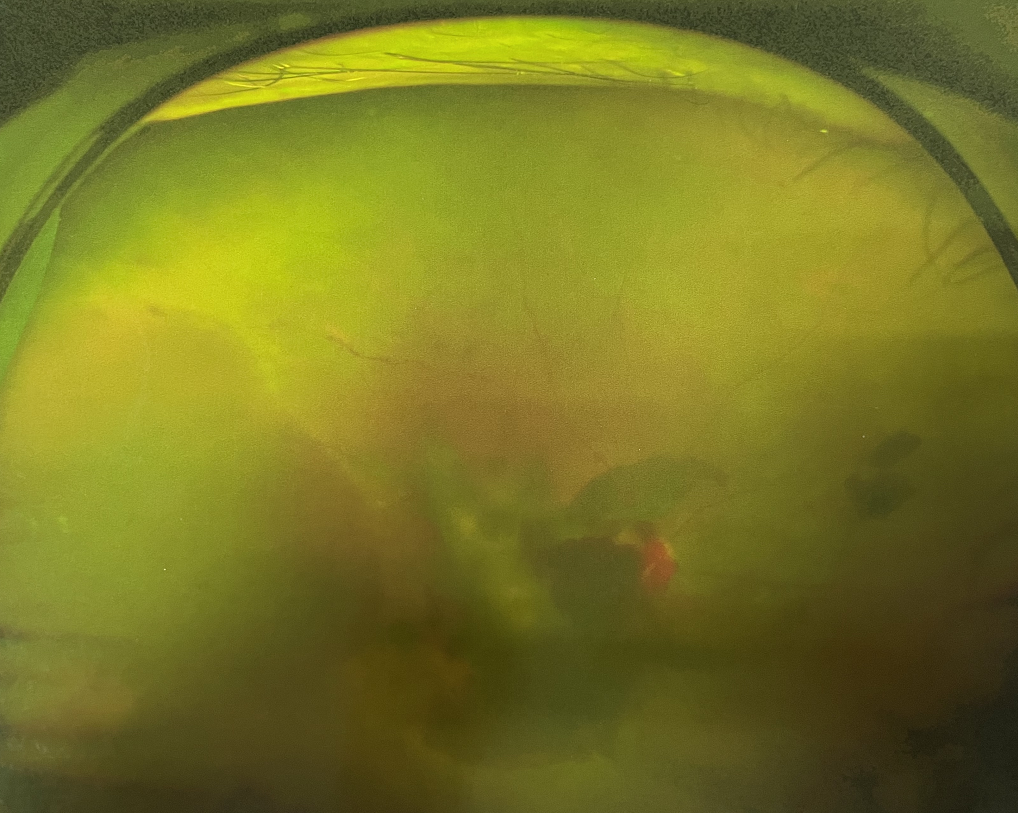

眼底出血多指玻璃體內,眼睛更深處的視網膜出血。通常情況下,肉眼難以發(fā)現(xiàn)眼底出血,而且發(fā)病初期眼睛也無明顯癥狀,只有借助專業(yè)的眼底檢查儀器才能觀察到異樣。那么眼底出血嚴重嗎?

誘發(fā)眼底出血的原因眾多,常見的有全身性血管病和血液病、視網膜血管異常、機械性阻塞、炎癥性疾病或免疫復合物侵犯血管壁等。

眼底出血嚴重嗎?其中,“三高”患者、高度近視患者和滲出性或濕性老年黃斑變性患者是眼底出血的高發(fā)人群。

醫(yī)生提醒,一旦眼睛出現(xiàn)視力下降、視物變形、視野缺損或眼前有黑影等視覺“異常”的情況,應及時到醫(yī)院進行眼底檢查,及早發(fā)現(xiàn),及早治療,以免貽誤病情。

眼底出血嚴重嗎?對于已出現(xiàn)黃斑水腫、視網膜新生血管的患者,根據眼底血管造影、oct等檢查結果,給予玻璃體腔注射抗VEGF藥物及激光治療,可以減輕黃斑水腫,使視網膜新生血管消退,以免進一步發(fā)生玻璃體出血、視網膜脫離等嚴重并發(fā)癥的出現(xiàn)。對于玻璃體出血者,傳統(tǒng)認為玻璃體出血3-6個月不吸收再進行手術干預,但近年來因為顯微手術設備及玻璃體切割技術已非常成熟,故對于1個月不吸收的玻璃體出血者就可以考慮手術,即手術時機應該具體情況具體分析,因人而異。